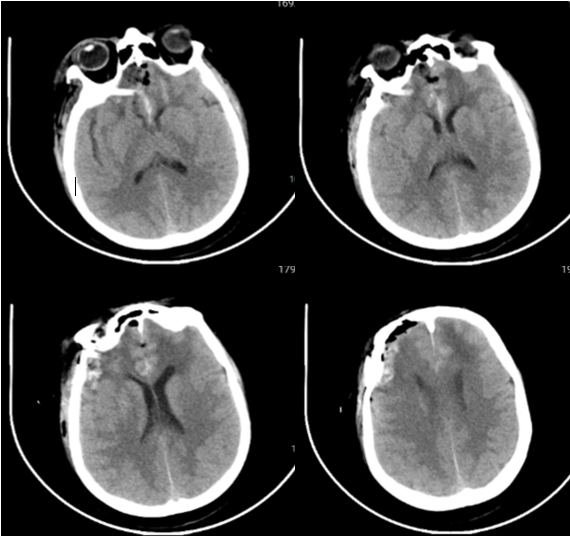

注:术后第一天CT显示额叶脑挫伤及水肿不重

手术前后比较:前颅底增生骨质处理情况

注:术后CT骨窗及三维重建